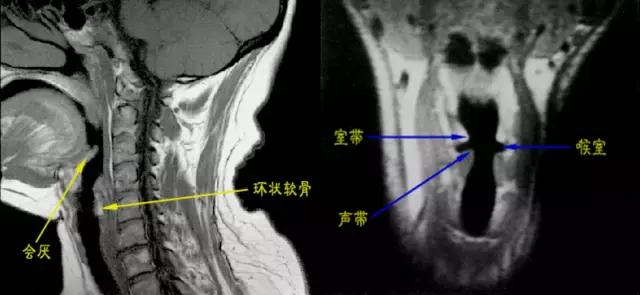

- 声门上区:声带之上,室带以上喉腔称为喉前庭。声带与室带之间的腔隙为喉室。室带(假声带),由室韧带、肌纤维及粘膜组成,前端起于甲状软骨前角的上中段内面,后端止于杓状软骨前上面。

- 声门区由声带构成,喉室下方由声韧带、肌纤维和粘膜构成,前端起于甲状软骨前角中段内面,后附着于杓状软骨声带突,厚约5mm。张开时出现一个等腰三角形裂隙称声门裂,发音时声带内收。

- 声门下区为声带下至环状软骨下缘以上的喉腔,正常气道与环状软骨间粘膜厚度不超过1mm。